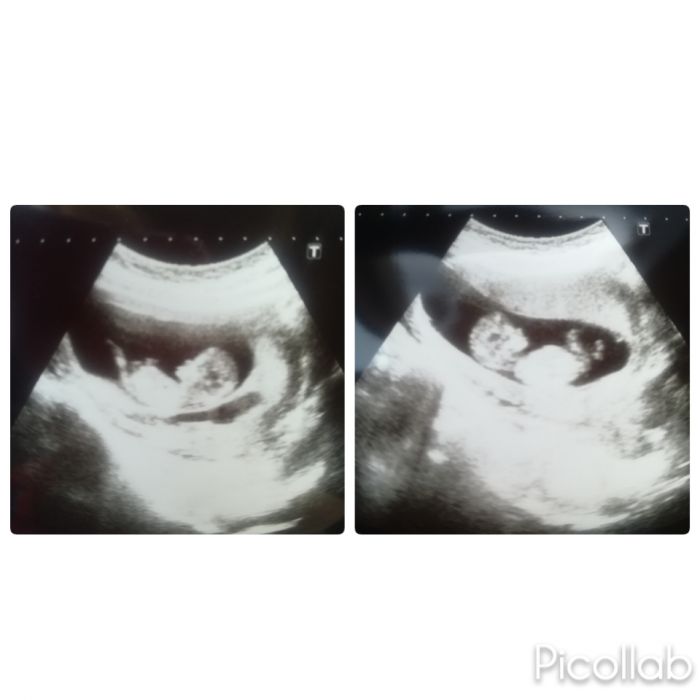

Já byla dnes na kontrole, už mám i průkazku, jsem 12+2tt a obě hezky rostou, na ultrazvuku nám mávali, jedno je hlavou doleva a druhé doprava asi aby na sebe mohli koukat .. Sranda

je to nádhera

Za týden nás čeká velký ultrazvuk, tak snad bude všechno v pořádku a už to řekneme i synovi